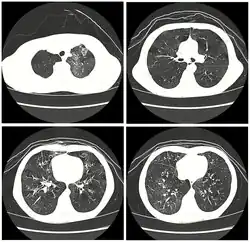

| High resolution CT scan showing bronchiolitis obliterans with mosaic attenuation, bronchiectasis, air trapping and bronchial thickening[3] | |

Early in the disease chest radiography is typically normal but may show hyperinflation.[6] As the disease progresses a reticular pattern with thickening of airway walls may be present.[4][6] HRCT can also show air trapping when the person being scanned breathes out completely; it can also show thickening in the airway and haziness in the lungs.[11] A common finding on HRCT is patchy areas of decreased lung density, signifying reduced vascular caliber and air trapping. This pattern is often described as a "mosaic pattern", and may indicate bronchiolitis obliterans.[6]